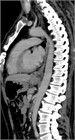

1. 嘔吐、腹痛、腹部膨満、便秘などを主訴に受診した場合には、腸閉塞の診断を行い、その原因として、内ヘルニアを念頭に置いておく必要がある。内ヘルニアによる絞扼性腸閉塞は重篤化するため、早期診断が重要である。早期診断には造影CTが有用であるため、行うことが勧められる(推奨度1 O)

1. 内ヘルニア・横隔膜ヘルニアと診断がつき次第、手術適応である。緊急的に行うか、待機的に行うかについては、造影CTで腸閉塞の状態を把握する必要がある。陥入した腸管を整復し、ヘルニア門を閉鎖もしくは開放する手術を行う(推奨度2 C)

1. 食道裂孔ヘルニアのある場合には胃食道逆流症(GERD)の合併率が高い。胃液の逆流による逆流症状を認め、治療はまず胃酸分泌抑制としてPPIによる治療を行う。内服治療だけでなく、食事指導、生活指導も重要である(推奨度1 M)